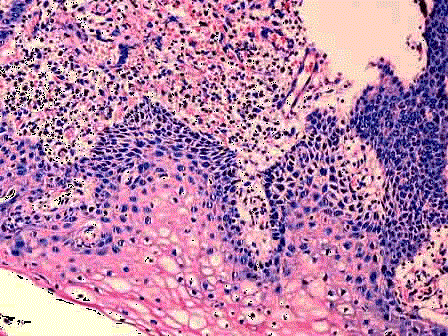

问题 女性,34岁,阴道分泌物增多并有异味,检查宫颈肥大,质硬,宫颈黏膜中度-重度糜烂,取宫颈黏膜活检,显微镜下如图。应诊断为 ( )

选项 A.慢性宫颈炎 B.宫颈息肉 C.CINⅠ D.CINⅡ E.宫颈原位癌

答案 A